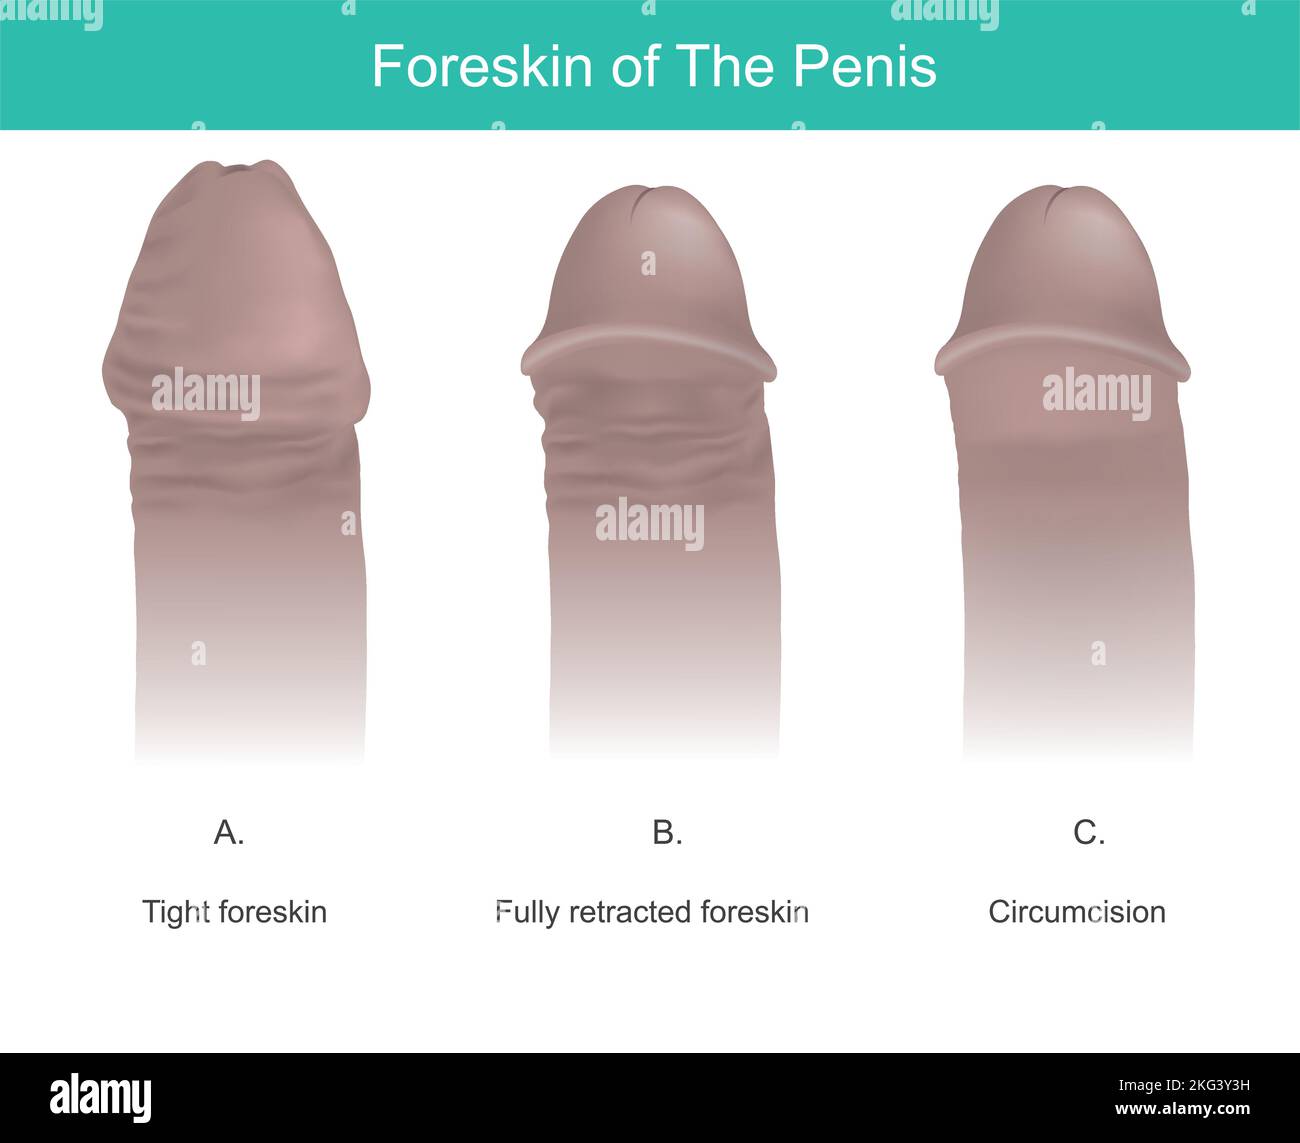

Liposuction Chirurgia, spiegare per attuare il trattamento di liposuction chirurgia nella zona della coscia. Illustrazione Vettorialehttps://www.alamy.it/image-license-details/?v=1https://www.alamy.it/liposuction-chirurgia-spiegare-per-attuare-il-trattamento-di-liposuction-chirurgia-nella-zona-della-coscia-image491811925.html

Liposuction Chirurgia, spiegare per attuare il trattamento di liposuction chirurgia nella zona della coscia. Illustrazione Vettorialehttps://www.alamy.it/image-license-details/?v=1https://www.alamy.it/liposuction-chirurgia-spiegare-per-attuare-il-trattamento-di-liposuction-chirurgia-nella-zona-della-coscia-image491811925.htmlRF2KG3Y3H–Liposuction Chirurgia, spiegare per attuare il trattamento di liposuction chirurgia nella zona della coscia.